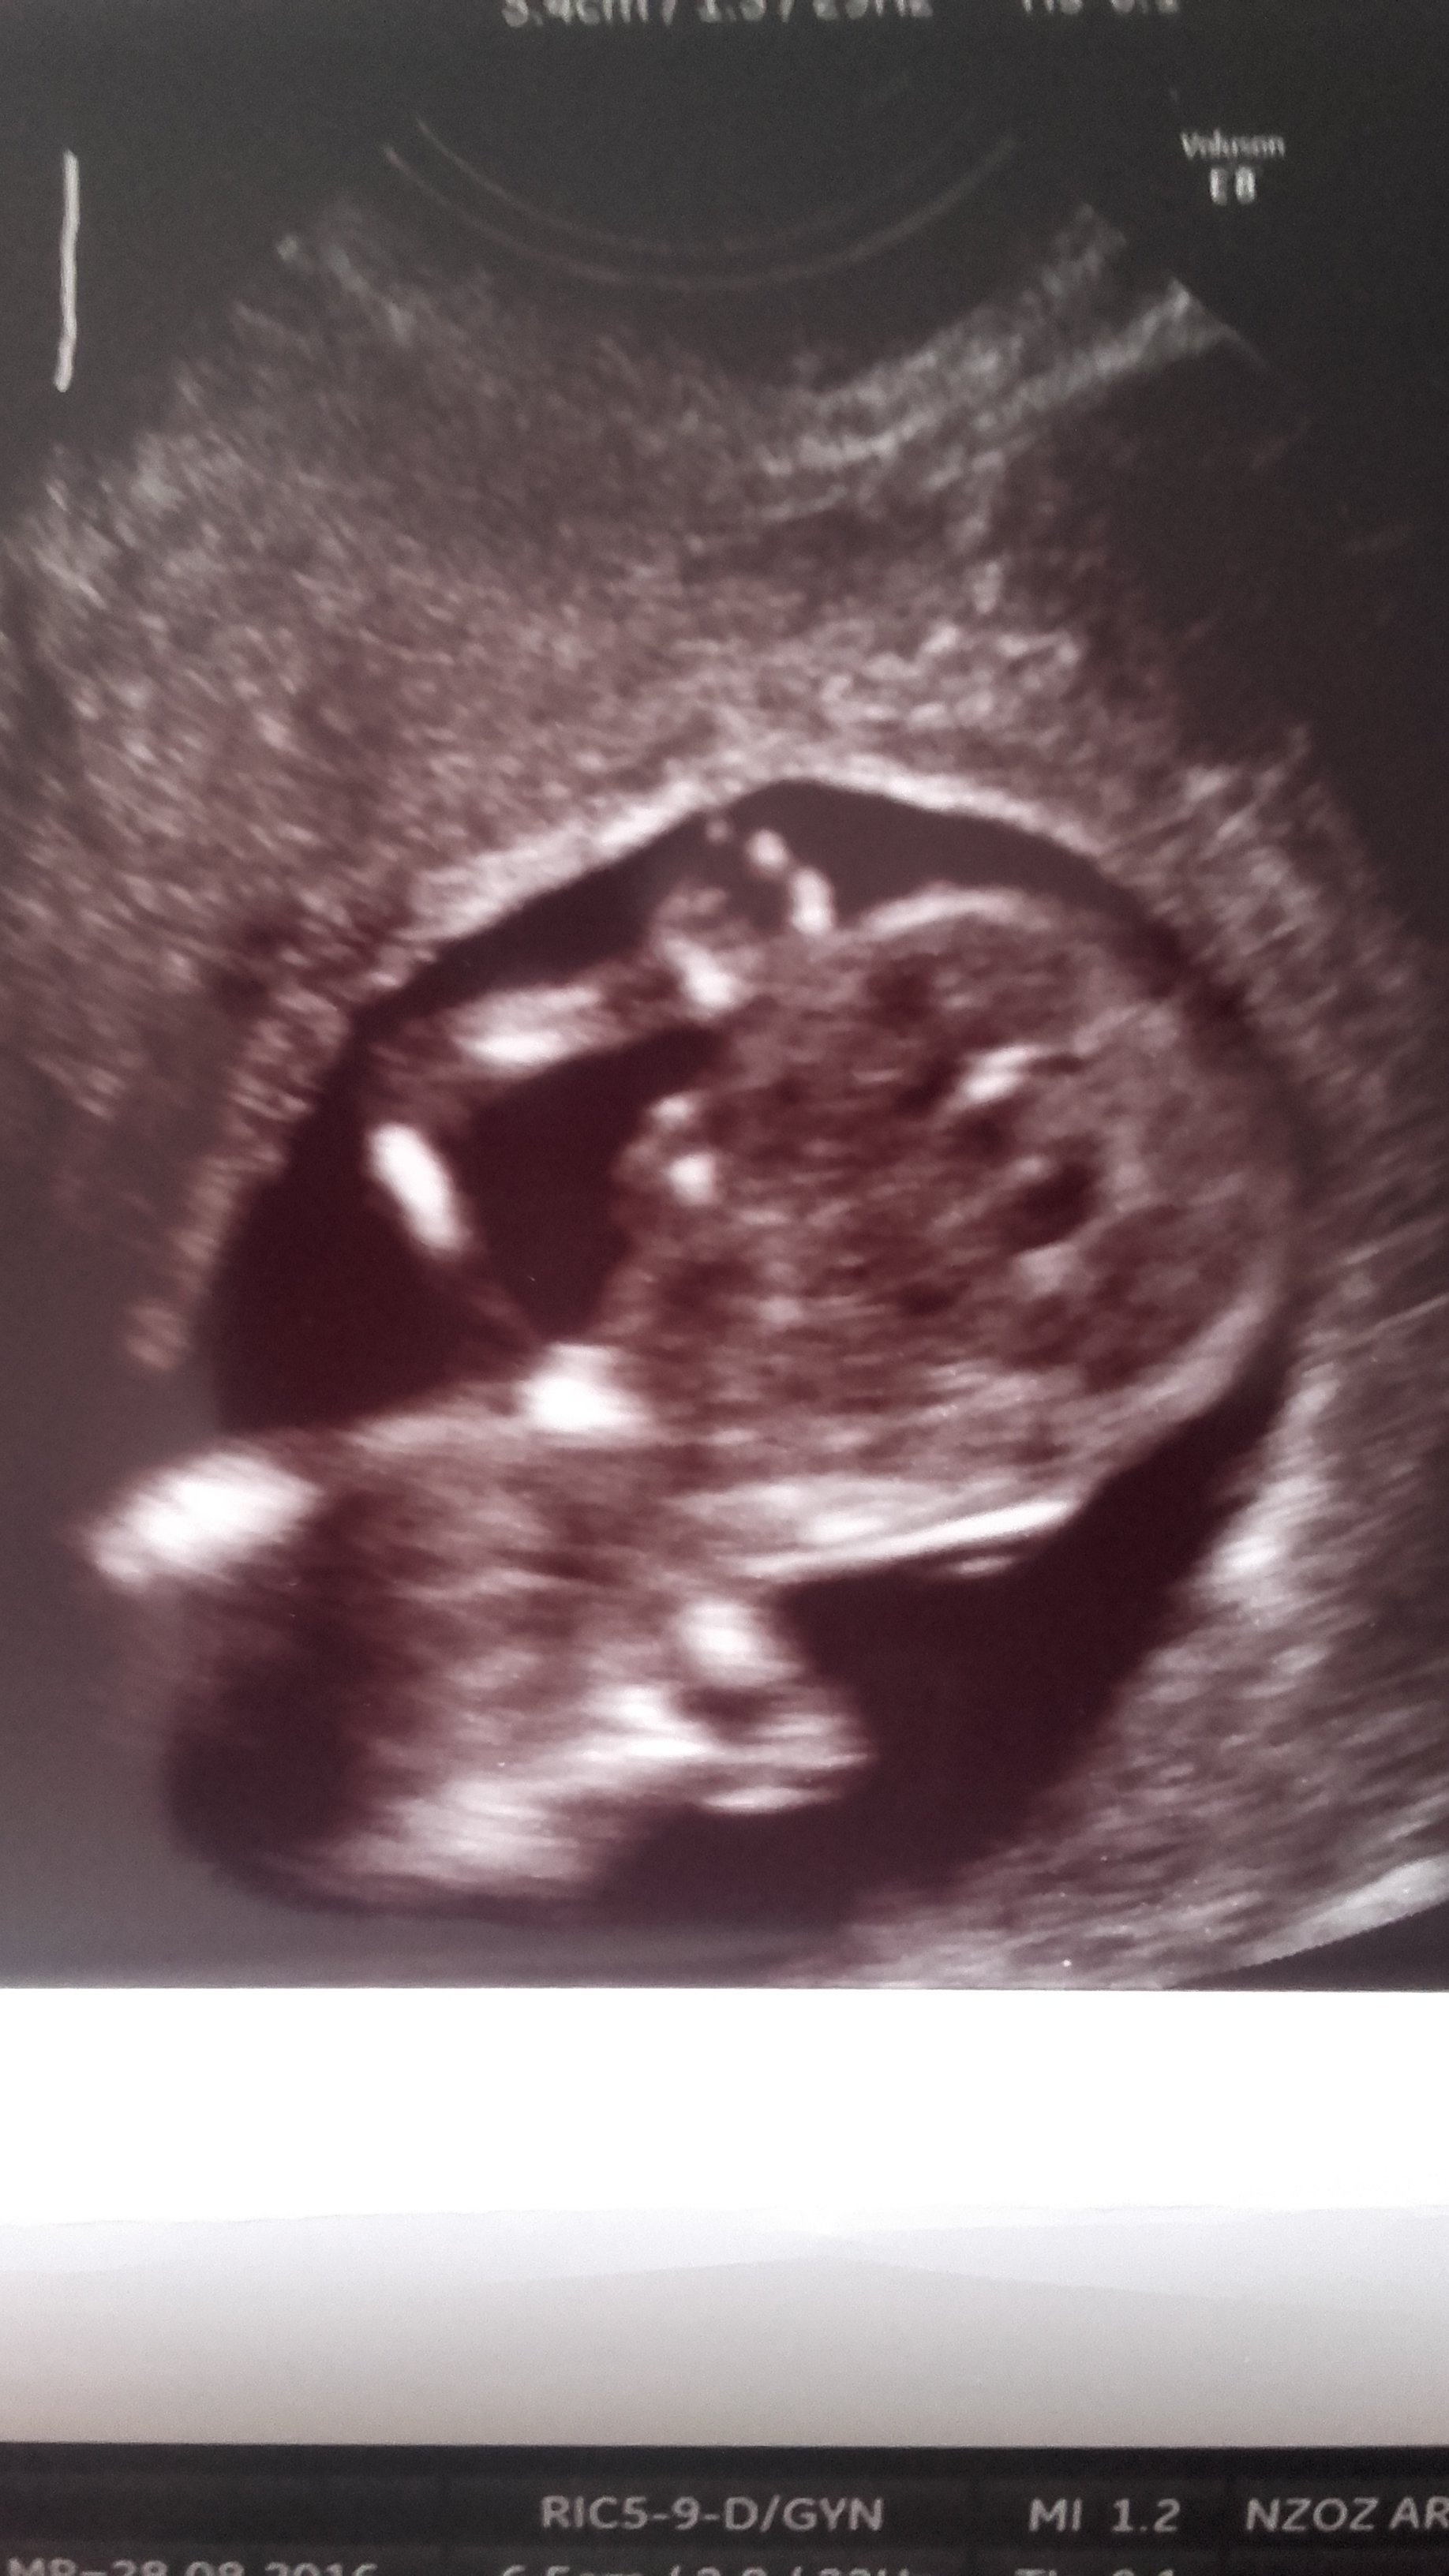

21:Marley - usg pecherzykowo- serduszkowe

ragonfly79 - usg serduszkowe

23: butterfly - wizyta serduszkowa